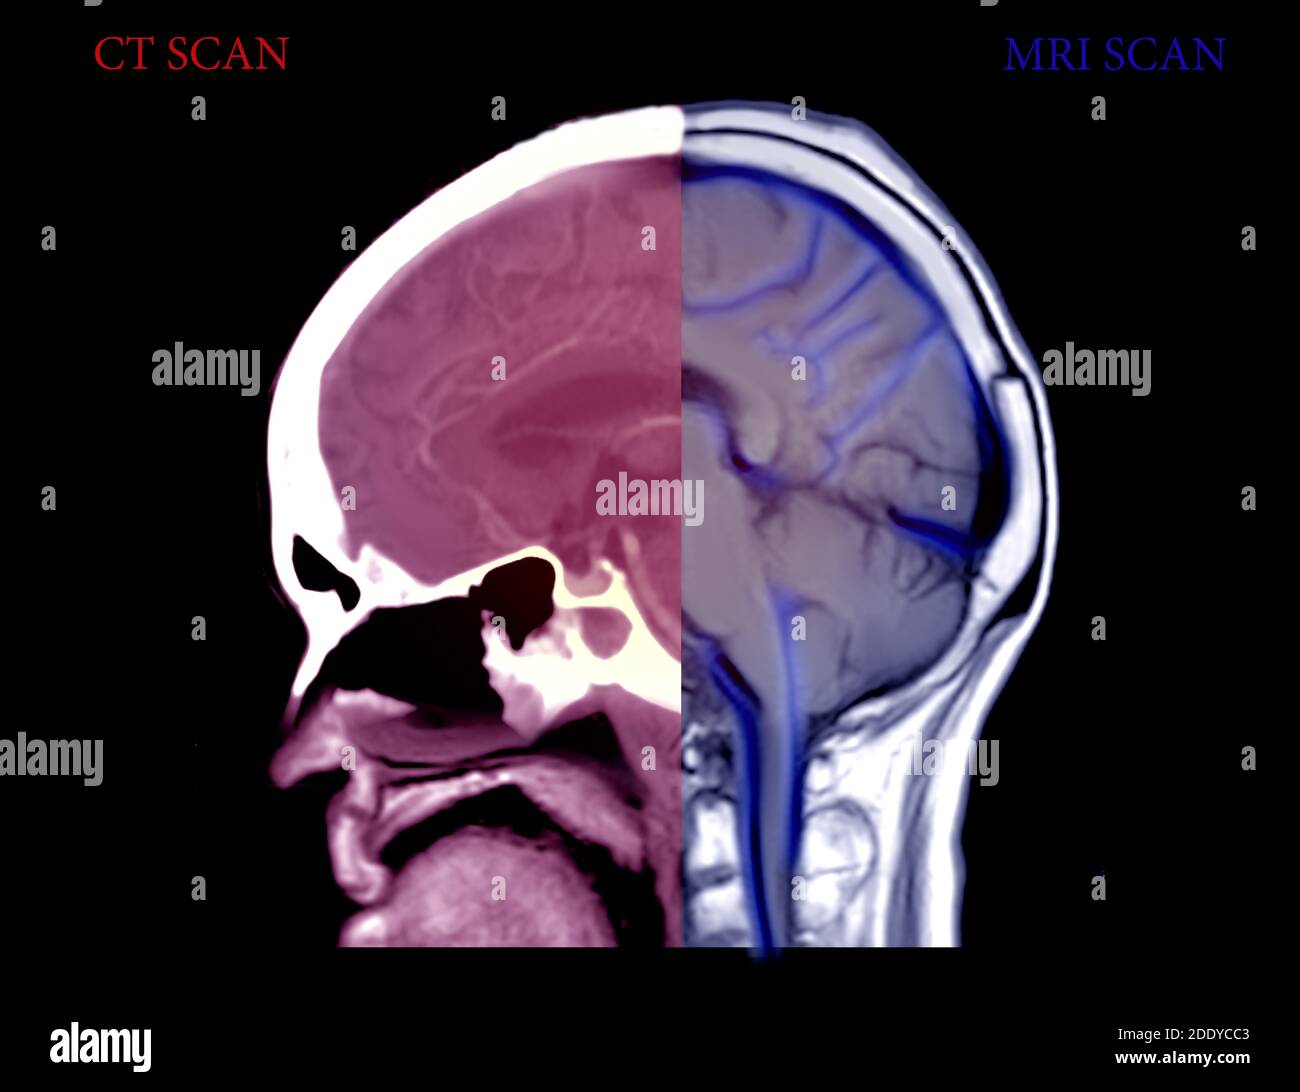

Comparez les vues sagittales CT Brain et MRI Brain . Concept d'arrière-plan médical. Banque D'Imageshttps://www.alamyimages.fr/image-license-details/?v=1https://www.alamyimages.fr/comparez-les-vues-sagittales-ct-brain-et-mri-brain-concept-d-arriere-plan-medical-image387221075.html

Comparez les vues sagittales CT Brain et MRI Brain . Concept d'arrière-plan médical. Banque D'Imageshttps://www.alamyimages.fr/image-license-details/?v=1https://www.alamyimages.fr/comparez-les-vues-sagittales-ct-brain-et-mri-brain-concept-d-arriere-plan-medical-image387221075.htmlRF2DDYCC3–Comparez les vues sagittales CT Brain et MRI Brain . Concept d'arrière-plan médical.